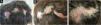

Three months after starting secukinumab, the patient experienced a significant worsening of psoriasis, with widespread lesions and two large erythematous and keratotic plaques on the scalp (occipital and parietal regions) with follicular pustules and areas suggesting fluctuation. Differential diagnosis included folliculitis decalvans, dissecting cellulitis, and other causes of cicatricial alopecia (Fig. 1). Biopsies were performed on both plaques, and samples were taken for bacterial and fungal cultures.

Histopathological analysis of the biopsies, processed in vertical and horizontal sections, revealed a significant increase in the telogen and vellus indices. Loss and atrophy of sebaceous glands, infundibular dilation with thinning of the follicular epithelium, and a dense perifollicular lymphocytic inflammatory infiltrate were observed without interface involvement. The epidermis exhibited psoriasiform acanthosis and parakeratosis. These histological findings were consistent with psoriatic alopecia (Fig. 2). Cultures were negative.